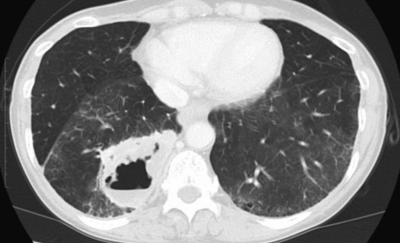

検査所見:血液所見:赤血球 350 万、Hb 9.8 g/dL、Ht 30 %、白血球 10,300、血小板 30 万。血液生化学所見:AST 19 U/L、ALT 15 U/L、LD 158 U/L (基準 176〜353)、γ-GTP 16 U/L (基準 8〜50)、総ビリルビン 0.4 mg/dL、総蛋白 7.2 g/dL、アルブミン 3.8 g/dL、尿酸 2.9 mg/dL、尿素窒素 11 mg/dL、クレアチニン 0.5 mg/dL、 Na 140 mEq/L、 K 4.0 mEq/L、 Cl 105 mEq/L、 Ca 8.9 mg/dL、Fe 20 μg/dL、TIBC 231 μg/dL (基準 290〜390)、フェリチン 643 ng/mL (基準 20〜120)、CEA 4.5 ng/mL (基準 5以下)。CRP 1.4 mg/dL。画像所見:上肺野(肺野条件)、中肺野(縦隔条件)、下肺野(肺野条件)及び上腹部の造影CTを別に示す。呼吸機能所見:現在と 20 歳時の膝蓋骨骨折手術前のフローボリューム曲線を別に示す。

実施した生検の結果では、いずれも肺腺癌の所見であった。患者に説明する内容として誤っているのはどれか。